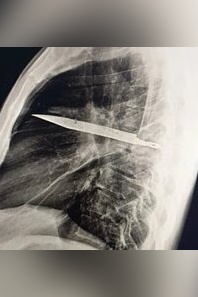

عکس| کشف شی عجیب در قفسه سینه یک مرد بعد از 8 سال؛ چاقویی که در بدن ریشه کرده